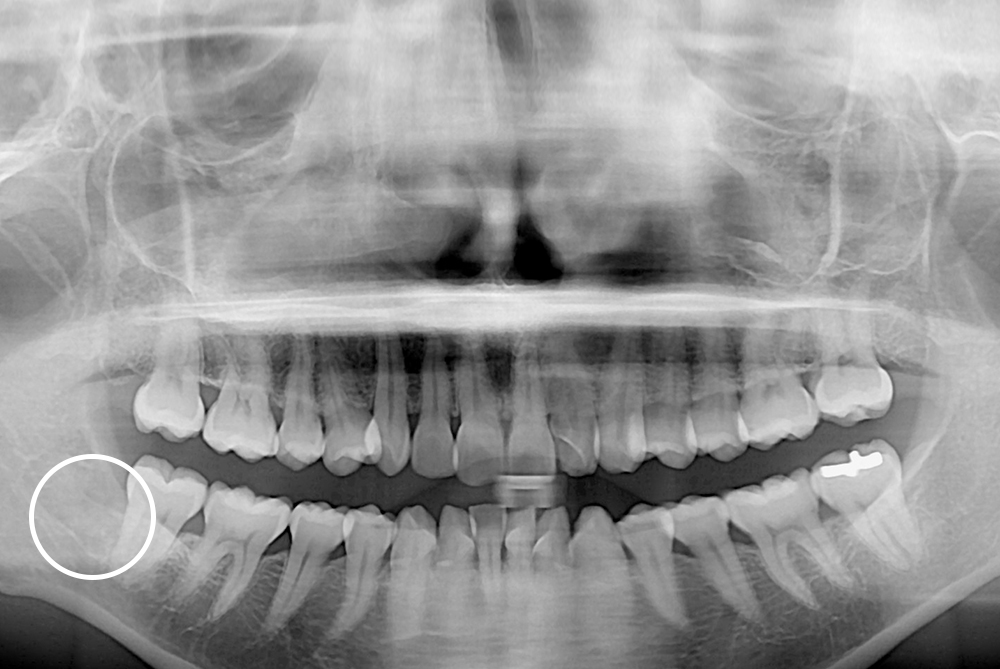

[사랑니] 매복 사랑니 발치

치료전 : 2019-04-03

세종치과는 구강악안면외과학 박사이신 원장님이 발치하는 치과입니다.